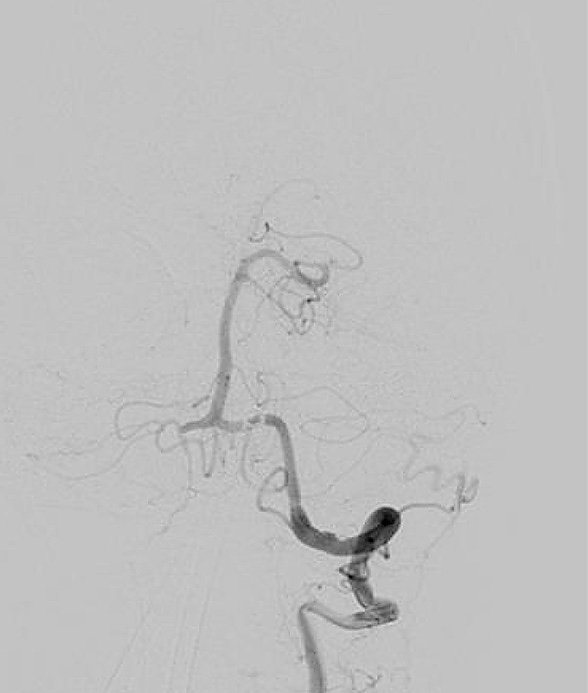

Bei der Subtraktionsangiografie wird eine Arterie im Ellbogen, Handgelenk oder (am häufigsten) in der Leiste punktiert. Über diese Punktion wird ein sehr flexibler Draht eingebracht und über diesen dann ein Katheter. Mit dieser Technik können sehr viele, auch sehr kleine, Gefäße, beispielsweise im Kopf, aber auch tumorversorgende Gefäße dargestellt werden. Mit der Angiografie können verstopfte Gefäße aufgeweitet werden, andere Gefäße, die beispielsweise bösartige Tumoren versorgen, dauerhaft verschlossen werden. Auch Gefäßerkrankungen wie die Verschlusskrankheit kann durch die Angiografie behandelt werden und Gefäßaussackungen (Aneurysmata) verschlossen werden. Wir führen als eine der sehr komplexen Interventionen die transarterielle Chemoembolisation durch, bei der der gefäßverschließende „Kleber“ mit einem Chemotherapeutikum verbunden ist, dass dann direkt in den (Leber)tumor eingebracht wird und dort auch verbleibt. Um eine Angiografie durchführen zu können, muss die Nierenfunktion über eine Blutentnahme geklärt werden, ebenso die Funktion der Schilddrüse. Außerdem ist es wichtig, die Blutgerinnungswerte zu kennen. Selbstverständlich wird jeder Patient ausführlich vor einer solchen Untersuchung individuell ärztlich aufgeklärt, weil hierbei auch Komplikationen auftreten können, wie Gefäßverletzungen, Blutergüsse und ungewollte Gefäßverschlüsse durch Verstopfungen (Thrombembolie), was je nach Untersuchungsbereich auch zu einem Hirnschlag (Apoplex) führen kann. Trotzdem ist die Angiografie aus der modernen Radiologie insbesondere bei interventionellen verfahren nicht wegzudenken. Als einzige Klinik in Nordthüringen haben wir eine Angiografie, die technisch auf exzellentem Niveau ist, weil wir zeitgleich aus zwei Röhren Bilder erstellen können, was Untersuchungszeit und Komplikationsrisiken deutlich verringert (biplane Subtraktionsangiografie).

Momentaufnahme während der Angiografie (Foto: SHK) Momentaufnahme während der Angiografie (Foto: SHK)